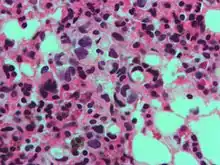

Células en anillo de sello

En histología, una célula en anillo de sello es aquella célula con una vacuola grande. El tipo maligno se observa predominantemente en carcinomas.

El nombre de la célula proviene su aspecto; las células en anillo de sello aparentan ser anillos de sello . Contienen una gran cantidad de mucina, la cual empuja al núcleo hacia la periferia de célula. El contenido de mucina en las células en anillo de sello imita la apariencia de un agujero para el dedo y el núcleo imita aspecto de la cara del anillo en perfil.